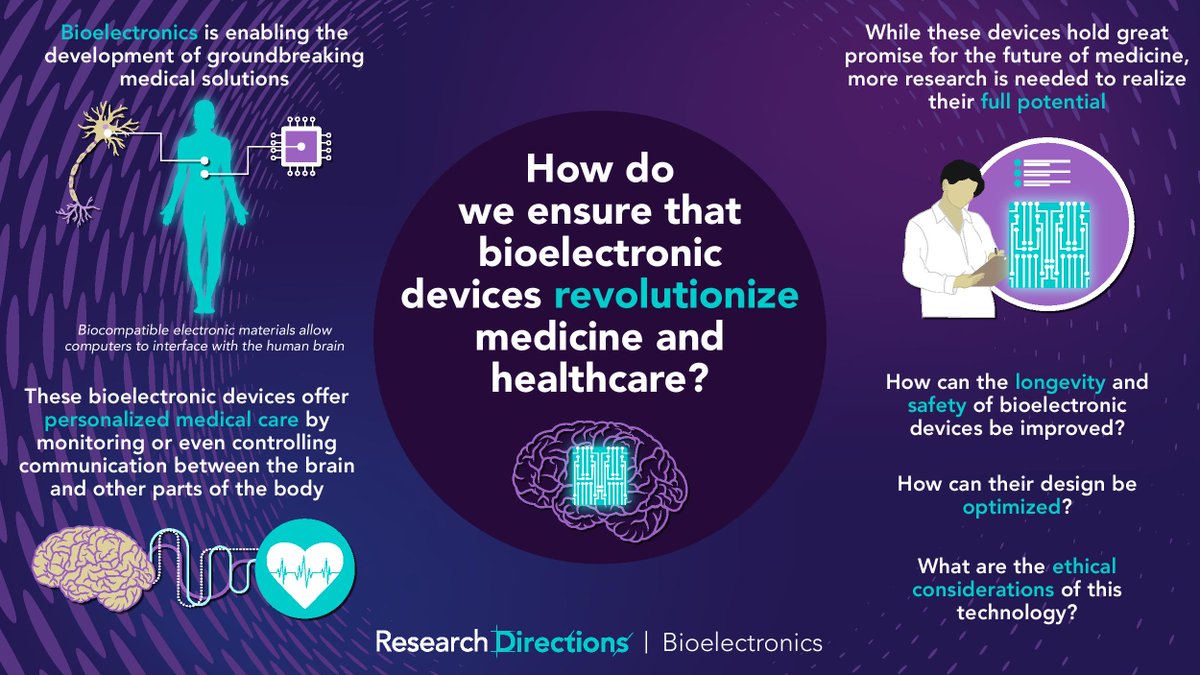

#RDBioelectronics welcomes contributions from researchers to answer this question from @sc_laboratories: 🟣How do we ensure that #bioelectronic devices revolutionize medicine and healthcare? Learn more about this question and how to contribute:cup.org/3pcKJ4o #bionics